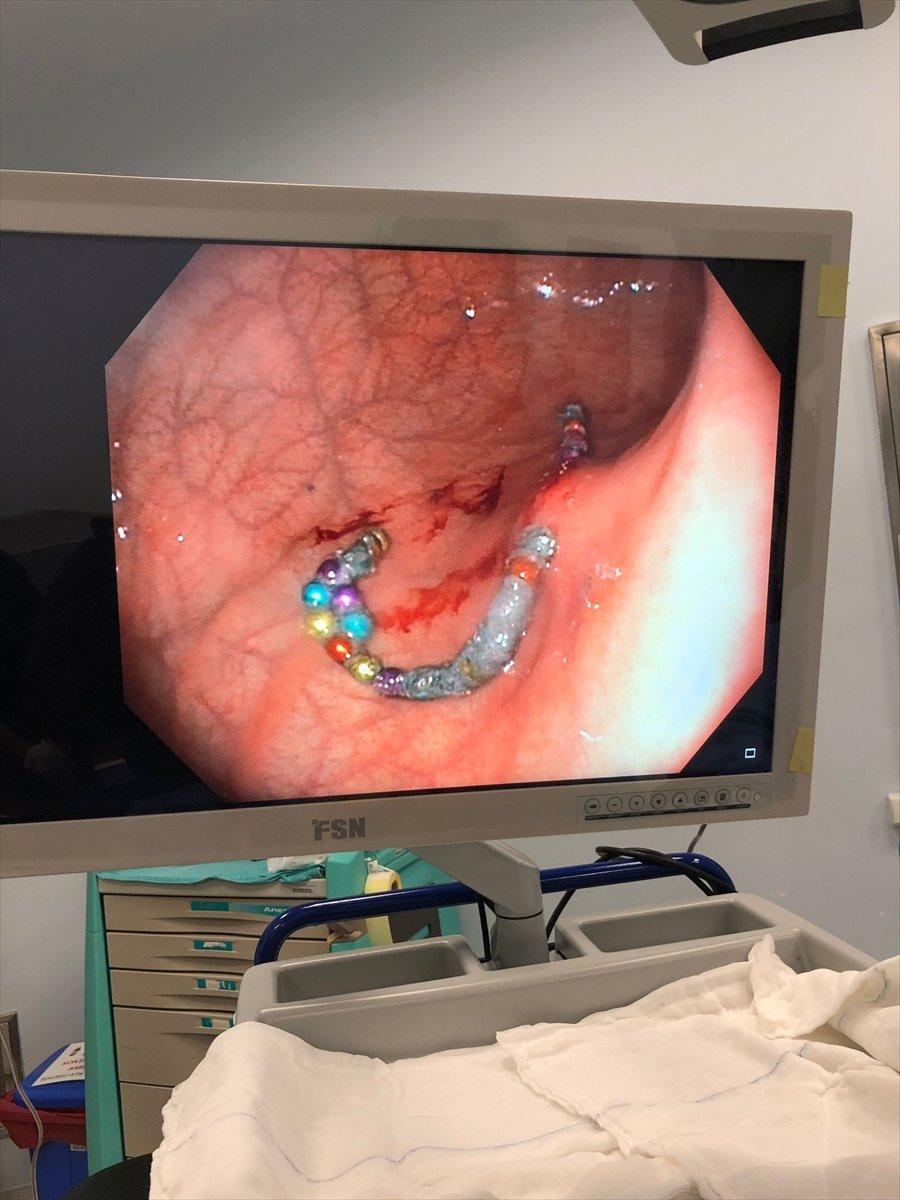

Pamukkale Üniversitesi Hastanesi'ne götürülen çocuk için burada acil ameliyat kararı alındı. Çocuk Gastroenteroloji Öğretim Üyesi Doç. Dr. Halil Kocamaz ve ekibi, Murat'ın midesindeki 5 milimetre çapındaki 17 boncuk mıknatısı yaklaşık 2 saat süren operasyonla çıkardı. Operasyonun ardından normal servise alınan Murat Özdemir'in tedavisi sürüyor.

Midedeki boncuk şeklindeki mıknatısların bir arada toplanması, röntgen ve endoskopi görüntüsüne de yansıdı.

"Operasyonda gerçekten midede boncuklardan oluşan bir halka olduğunu gördük. Bu yuvarlak cisimlerin midenin içini delerek gömüldüğünü fark ettik. Biz bunu çıkartmaya çalıştığımızda da bizim metal aletlerimize mıknatısların yapıştığını gördük. Dolayısıyla mıknatıs olduğunu anladık. Çocuklarda mıknatıs yutmak çok tehlikeli bir durumdur. Bu cisimlerin yaklaşık 1 aydır midede olduğunu tahmin ediyoruz."